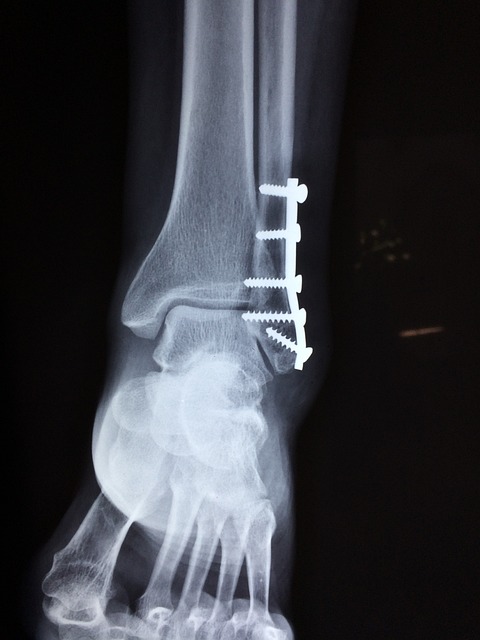

정복이 완료되면, 다음으로는 고정 단계가 진행됩니다. 고정은 뼈가 원래 위치에 잘 유지될 수 있도록 부목, 석고, 금속판, 혹은 나사 등을 사용하는 과정입니다. 석고 고정은 주로 단순 골절에 사용되며, 부러진 뼈를 안정적으로 고정해 뼈가 자연적으로 치유될 수 있도록 돕습니다. 복합 골절이나 고정이 어려운 경우에는 내부 고정으로 금속판이나 나사를 뼈에 삽입하여 수술적인 고정을 할 수 있습니다.

골절이 고정된 후에는 회복 단계로 넘어갑니다. 뼈가 자연적으로 치유되는 데는 4주에서 12주 정도가 소요되며, 나이, 건강 상태, 골절 부위에 따라 차이가 날 수 있습니다. 회복 기간 동안에는 주기적인 X-ray 촬영을 통해 뼈가 제대로 붙고 있는지를 확인합니다.